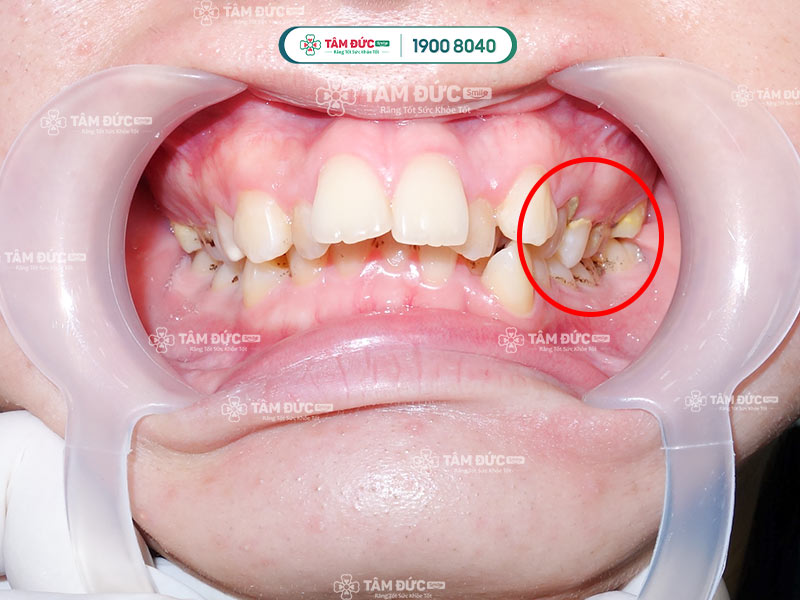

Cao răng tích tụ lâu ngày dẫn đến sâu viêm

Cao răng làm hỏng răng nhanh chóng

Vôi răng gây nên mùi hôi khó chịu

Cận cảnh cạo vôi răng cho khách hàng 35 năm chưa từng cạo vôi răng.